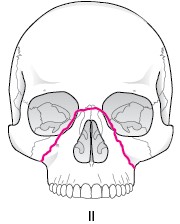

LefortU型骨折

鼻骨−上顎骨前頭突起−涙骨−篩骨−眼窩底−上顎骨頬骨縫合部−翼口蓋窩−翼状突起に達する骨折です。

症状としては、一時的意識喪失、眼窩周囲皮下出血、非出血、顔面腫脹、眼窩下部に段差、複視、上唇知覚異常、

咬合不全、上顎歯列 がー塊として動くなどです。